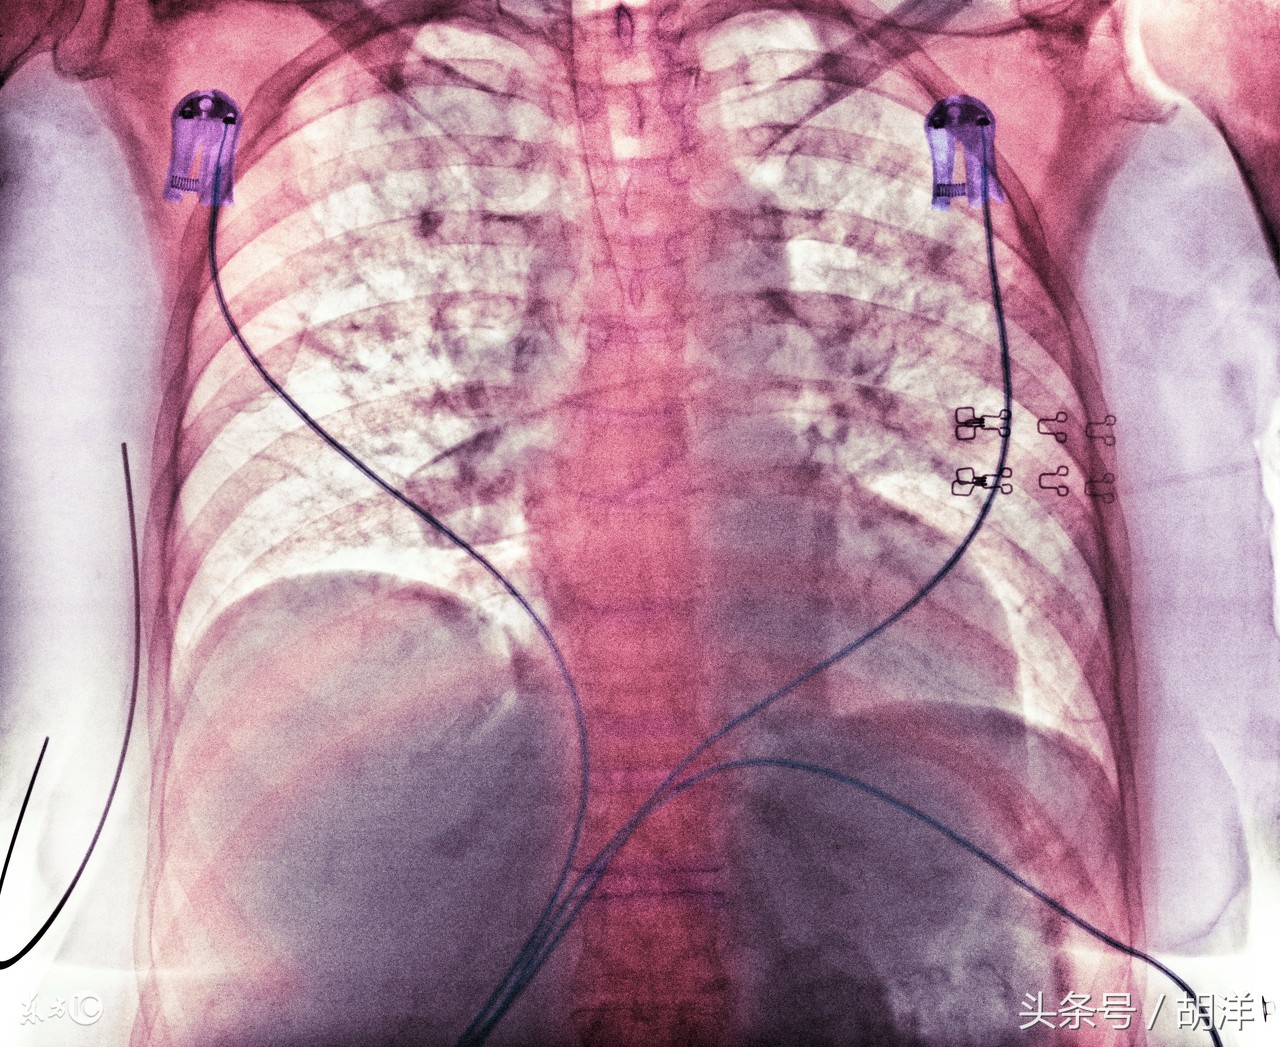

第2是气管镜检查

气管镜检查是用一根能够扭曲的纤维镜,从鼻子进入呼吸道,直接插入肺部检查病灶部位的检查方法。除了能够直观的看到肺内病灶的形态,还能够进行刷检和灌洗。取出来的标本很多,能够检查到相应的病源体,比痰液检查的阳性率更高。